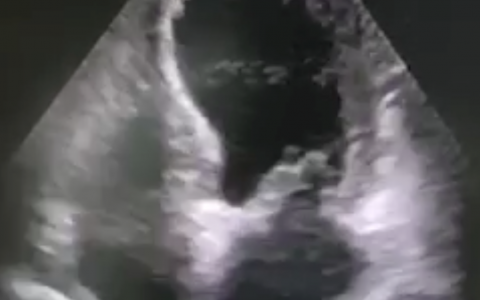

俯卧位前后对比

使用EIT来查看

经验:俯卧位使用呼吸机时候,提供一定的PEEP和驱动压,不要快速下降,等待肺完全张开后调整压力。不要只关注二氧化碳分压的水平。